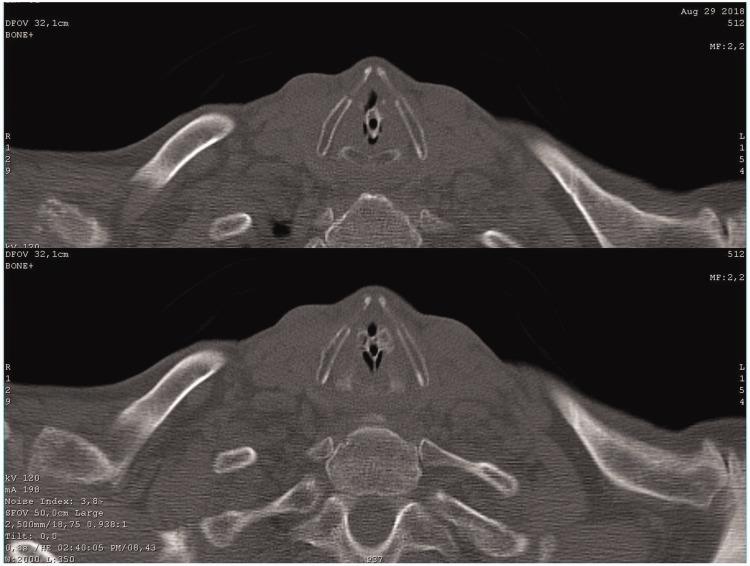

Laryngotracheal foreign body: chicken neck bone.

We herein present a case involving a 78-year-old patient who had aspirated a laryngotracheal foreign body 3 days prior to hospital admission. The patient had severe congenital intellectual disability; however, no agitation, suffocation, or death occurred despite almost complete laryngeal obstruction. The laryngotracheal foreign body was removed by tracheotomy and suspended microlaryngoscopy.

我们在此报告一例病例,患者为78岁老人,入院前3天吸入喉气管异物。该患者患有严重先天性智力残疾;然而,尽管喉几乎完全阻塞,但未发生躁动、窒息或死亡。通过气管切开术和悬吊式显微喉镜取出了喉气管异物。